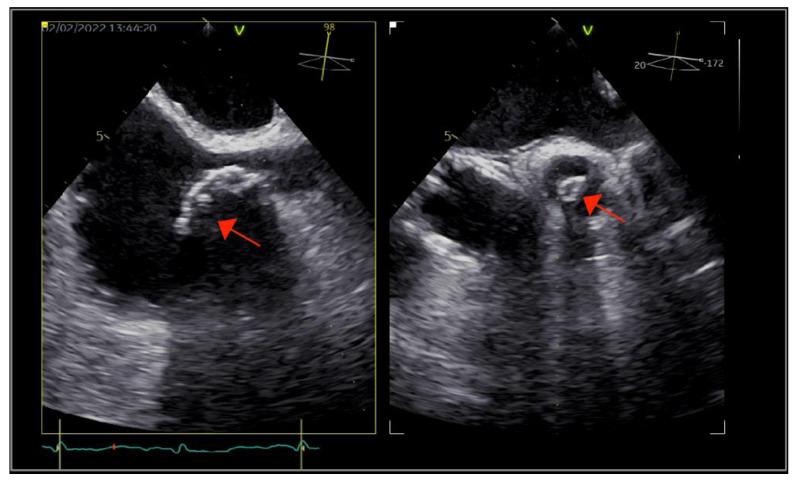

is a rare yet particularly aggressive infective endocarditis pathogen. We describe a case of successfully managed double-valve infective endocarditis, in which the presumed source of bacteremia was a long-term tunneled central venous catheter used for hemodialysis.

是一种罕见但特别侵袭性的感染性心内膜炎病原体。我们描述了一例成功治疗的双瓣膜感染性心内膜炎病例,该病例菌血症的疑似来源是用于血液透析的长期隧道式中心静脉导管。